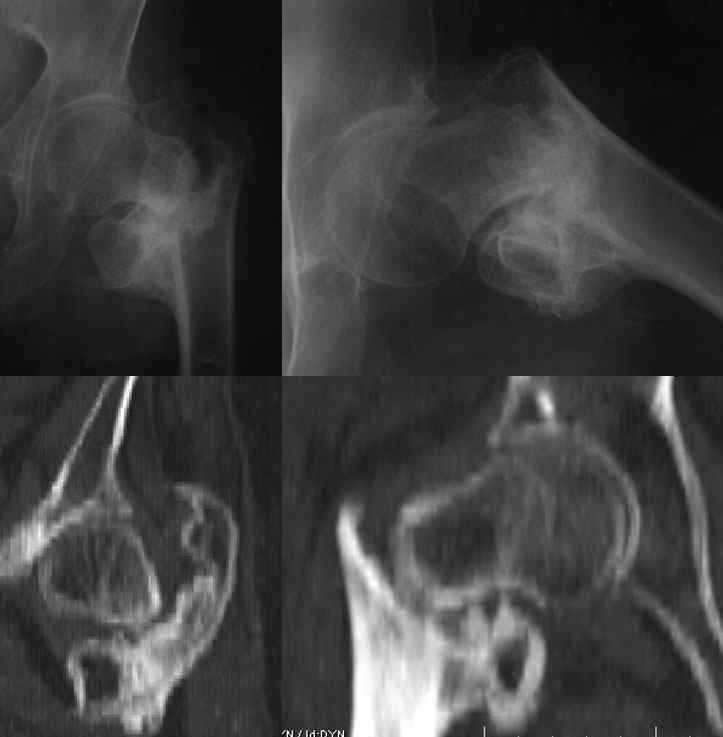

Уважаемые коллеги!Прошу вашего совета. Больная 61 год, травма бытовая в августе 2009г. Упала с высоты около 3 метров на область левого тазобедренного сустава. За медицинской помощью не обращалась. После уменьшения болевого синдрома больная начала передвигаться с помощью стула. В дальнейшем перешла на ходьбу без вспомогательных средств.

При СКТ исследовании: ложный сустав шейки левой бедренной кости в латеральном отделе с диастазом до 4,0 мм. Сросшийся чрезвертельный перелом бедренной кости с удовлетворительным стоянием и выраженной костной мозолью.При денситометрическом исследовании: данные соответствуют выраженной остеопении.